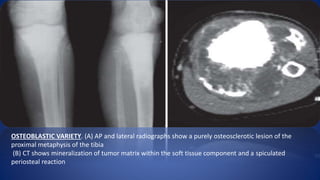

OSTEOBLASTIC VARIETY. (A) AP and lateral radiographs show a purely osteosclerotic lesion of the

proximal metaphysis of the tibia

(B) CT shows mineralization of tumor matrix within the soft tissue component and a spiculated

periosteal reaction